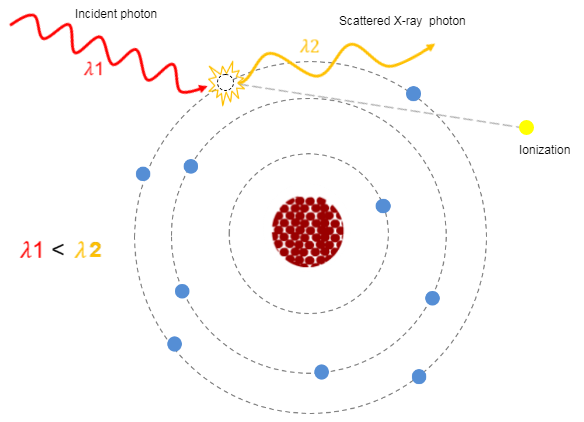

Attenuation is one of the physical principles of radiation interaction. If you recall, it is the reduction in the number of x-ray photons in the beam, and the subsequent loss of energy as the beam passes through the matter (or patient in this instance). In CT, as in diagnostic radiology, the attenuation is dependent on the type of tissue being scanned, such as the soft tissue, the bone, the blood or the muscle. Each type of tissue attenuates a different amount of photons which results in image differences on the finished scan. The denser the tissue, the more the attenuation of the beam.

It is important to know that X-ray penetration is an exponentially decreasing function of patient thickness. Thus, large patients will need a much larger dose. We use higher kVp to penetrate large people, large bony people, and bone. As we increase kVp, more of the beam penetrates the tissue with higher energy so they interact more by the Compton effect. This produces more scatter radiation which increases image noise, reduces contrast and increases the dose.